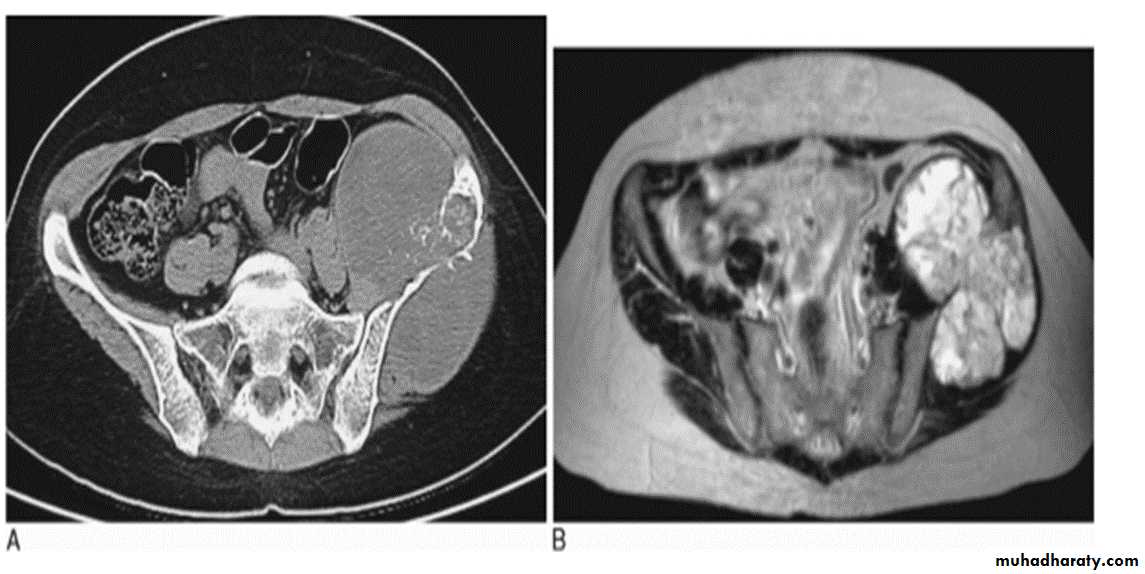

Chondrosarcoma :

Age: 30-50yrs.Site: pelvic bones, scapula, humerus, femur.

May arise as malignant degeneration in cartilage cap of osteochondroma (1%) and in its benign counterpart enchondroma .

Findings:

Ill-defined expanding lytic lesion

Flecks of calcification.

May have periosteal reaction.

Large extra osseous component.